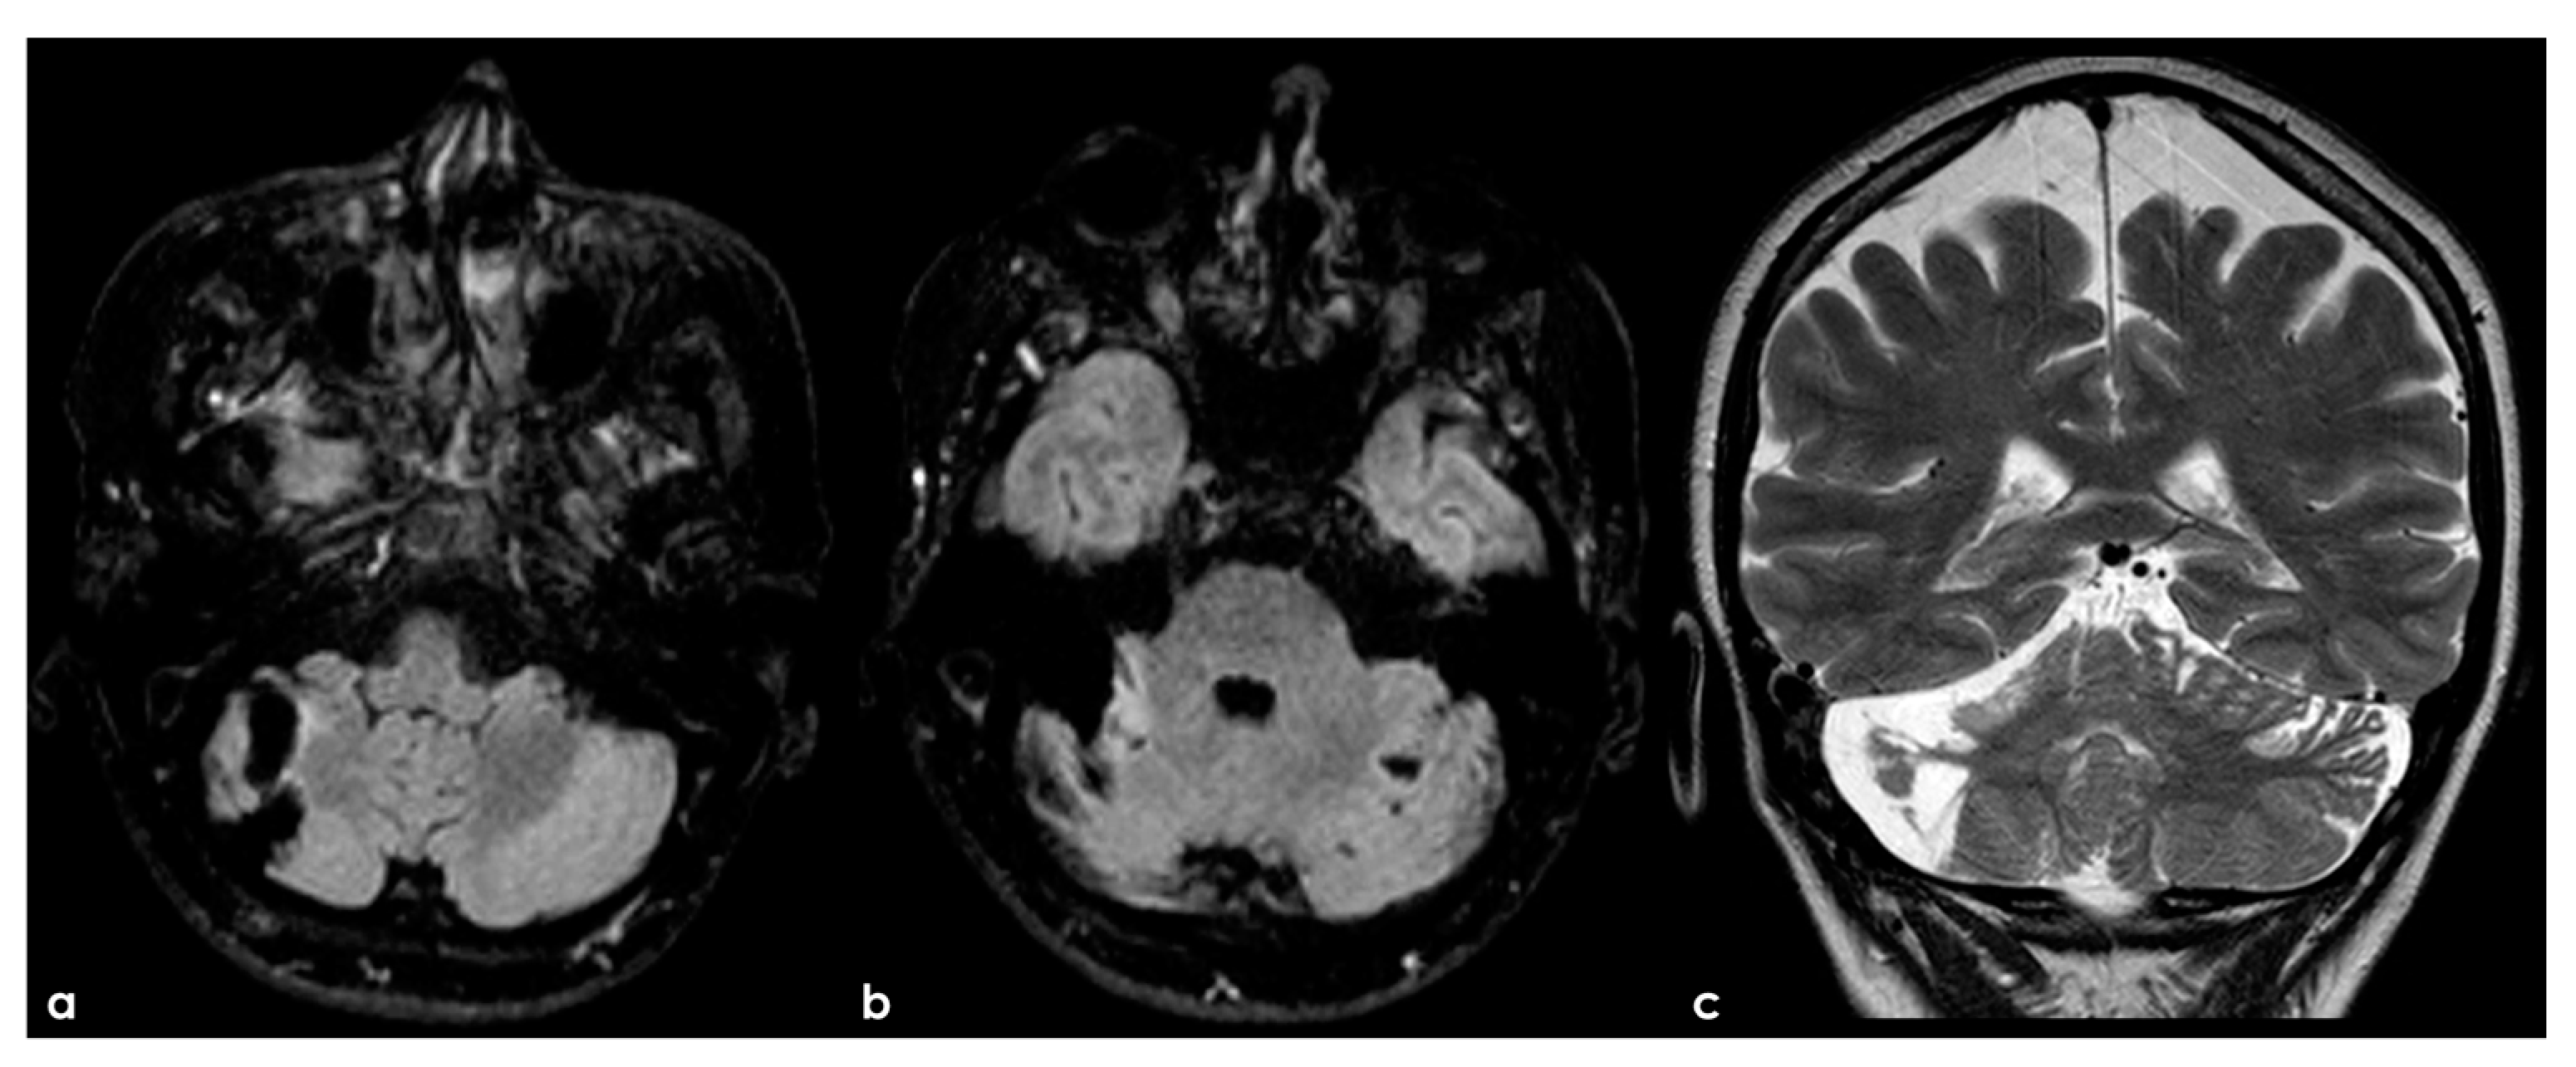

Figure 3.

A remote ischemic lesion in the right MCA territory is illustrated in the axial FLAIR sequence of the brain MRI (panel (a–c)) with the corresponding vascular imaging on a CT angiography with minimum intensity projection/multiplanar reconstruction (MIP/MPR) (panel (d,e)) in the coronal and axial plane, respectively. M1 MCA on both sides is occluded with a tiny network of small vessels partially contributing to supply M2 MCA.

Figure 4.

Digital subtraction angiography (DSA) of the same patient as in Figure 3 from a (right) (panels (a,b)) and (left) (panels (c,d)) ICA injection in PA view. Panels (a,c) are an early arterial phase, and panels (a,b) are a mid– late arterial phase. On both sides, the M1 MCA after its origin appears steno-occluded and is substituted by a network of collateral vessels involving the perforating arteries.